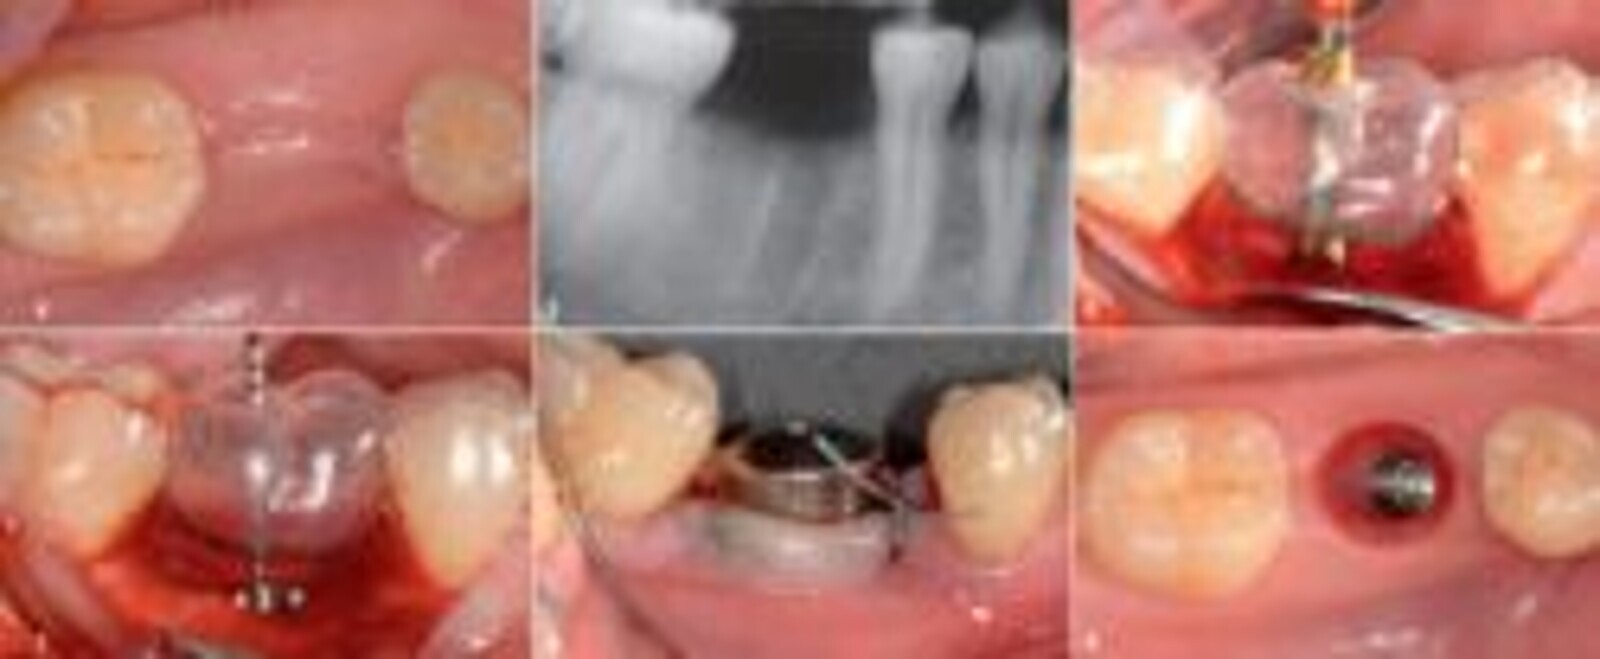

图1:46牙垂直骨折。探查可见一窄而孤立的远中裂沟,深度大于15毫米。

图2:在X线片上,沿远中根的远中壁上可以观察到垂直根折典型的J形投射影。

图3:拔牙时未损伤牙槽骨壁。不使用移植材料,对牙槽窝进行刮除和缝合。

图4:愈合8周后,拔牙区软组织完全愈合。

图5:八周后,牙槽骨形成量可以进行种植。

图6:使用外科支架,以计划修复的牙颈部外形高点作为参考点,在3D辅助下合适的位置进行截骨术。

图7:种植体位于计划修复的牙颈部轮廓向根尖3mm,近远中侧对称,偏舌侧2mm,以保留支撑软组织的颊骨。

图8:放置一个7mm的愈合基台,引导软组织达到最佳愈合状态。

图9:六周后移除愈合基台,并将印有种植体位置和软组织形状的最终印模与对侧模型一起送至牙科实验室。